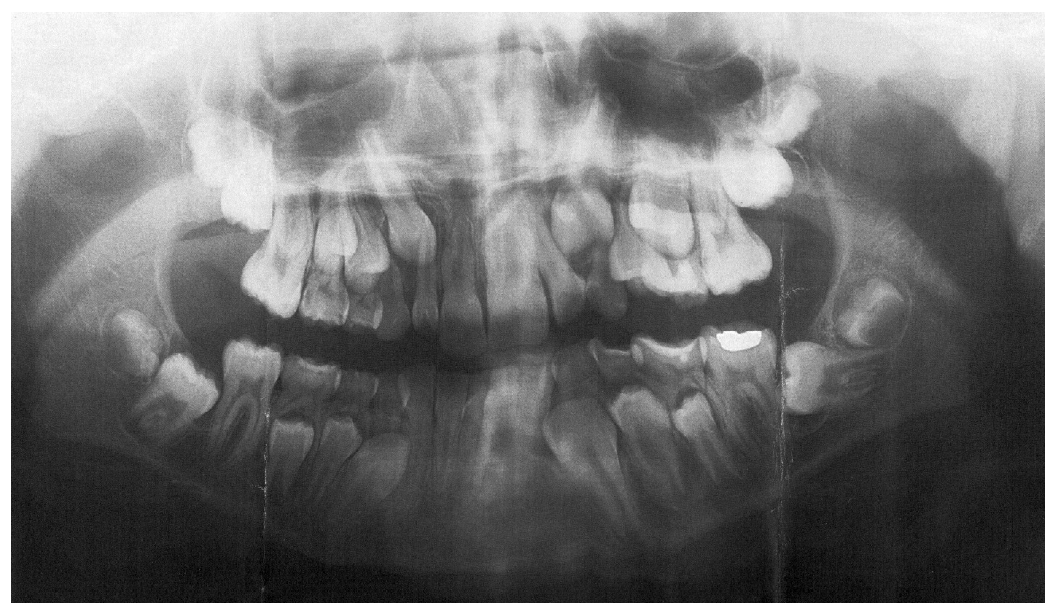

Mandibular Second Molar Impaction-Part II: Etiology and Role of the Third Molar

3. Results